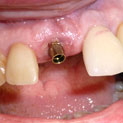

En estos casos han sido tratados con la filosofía de all-at-once, en la

misma sesión: